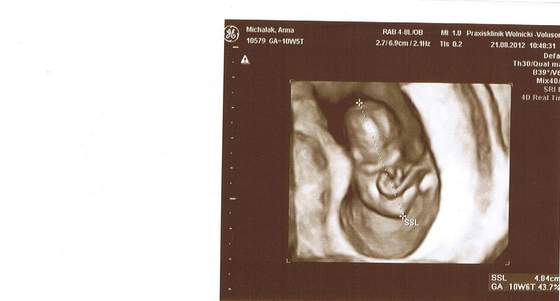

Zobacz załącznik 506927 18+2 wg OM